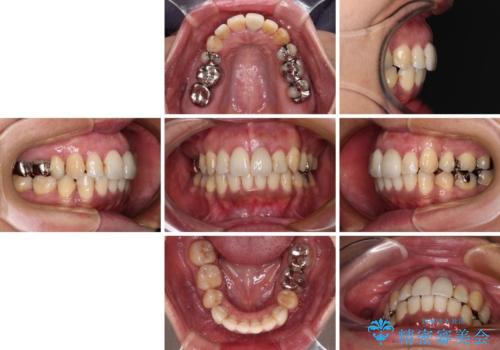

口元を引っ込めることができたため、口を閉じるときに力が入っていて皺のよっていた顎先も、スムーズに閉じられるようになったことで力がかからなくなりました。

変色して気になっていた前歯も、オールセラミッククラウンで自然な色合いにすることができました。